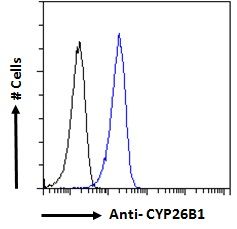

100 μl, 200 μl, 50 μlGoat anti-CYP26B1 Antibody [orb19329]

ELISA, FC, IHC

Canine, Human, Mouse, Rat

Goat

Polyclonal

Unconjugated

100 μg